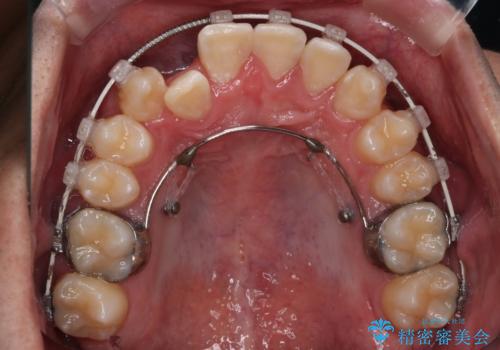

【審美装置】前歯の反対咬合改善

- 前歯の歯並びと噛み合わせを主訴に来院されました。

左右の噛み合わせが反対咬合であることと下顎の皮質骨が薄いため治療計画をしっかりと立てて行う必要のあるケースでした。

その点を考慮して、リンガルアーチを用いて奥歯を遠心移動し、前歯にIPR(歯と歯の間を削る処置)を行うことでスペースを作って歯並びを整えていく計画を立てました。

リンガルアーチを用いて奥歯を遠心移動し、前歯にIPR(歯と歯の間を削る処置)を行うことでスペースを作って歯並びを整えていく計画を立てました。